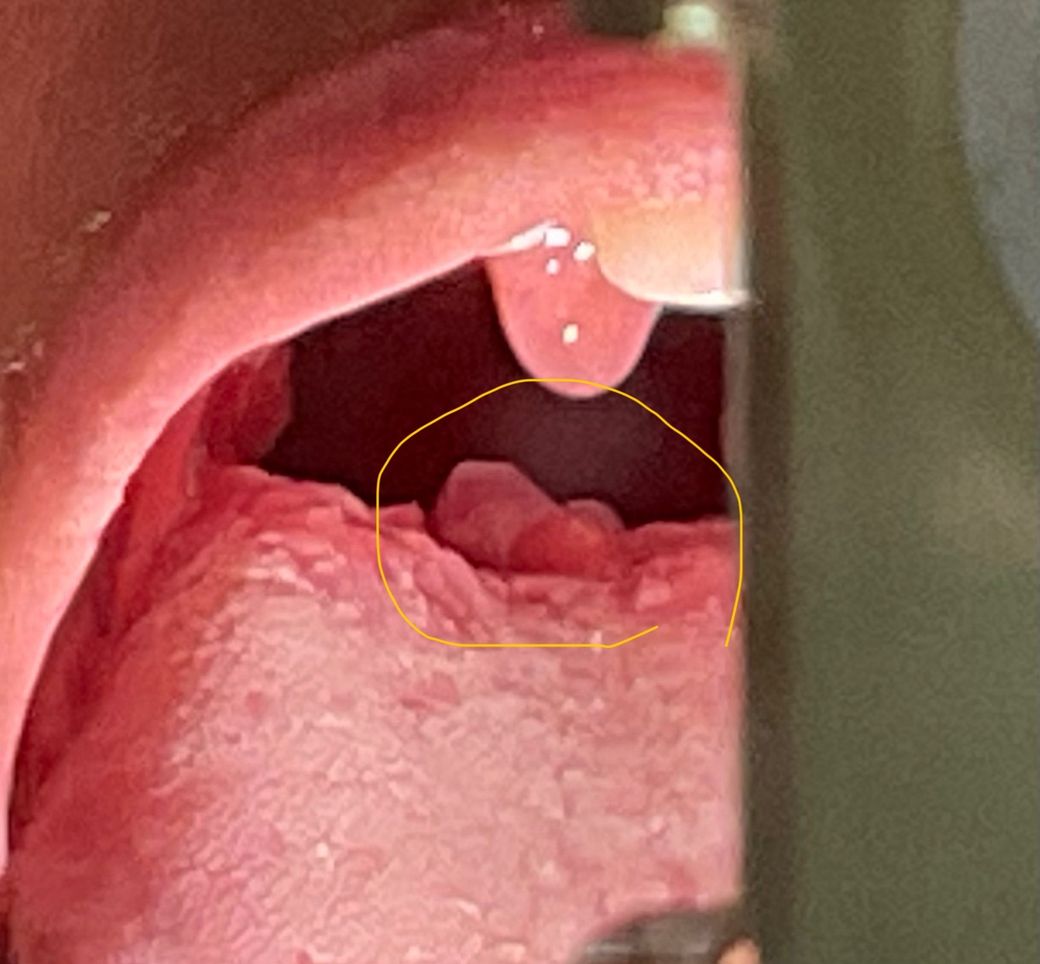

편도염걸렸는데 설편도염은 언제 회복 될까요?

편도염이 있다가 이비인후과 가서 약먹고 있다가 몸살이랑 오한증상으로 내과가서 새로처방 받은 약을 먹고 있는데 설편도염도 음식을 삼킬려면 힘든데 언제쯤 괜찮을 까요? 설편도염이 가운데 중앙에 생겼는데 약으로 괜찮아 질까요?(약은 펠프스정, 아모크라정375밀리그램, 소담캡슐 200mg,프리비투스현탁액8ml 총 5일치 약)